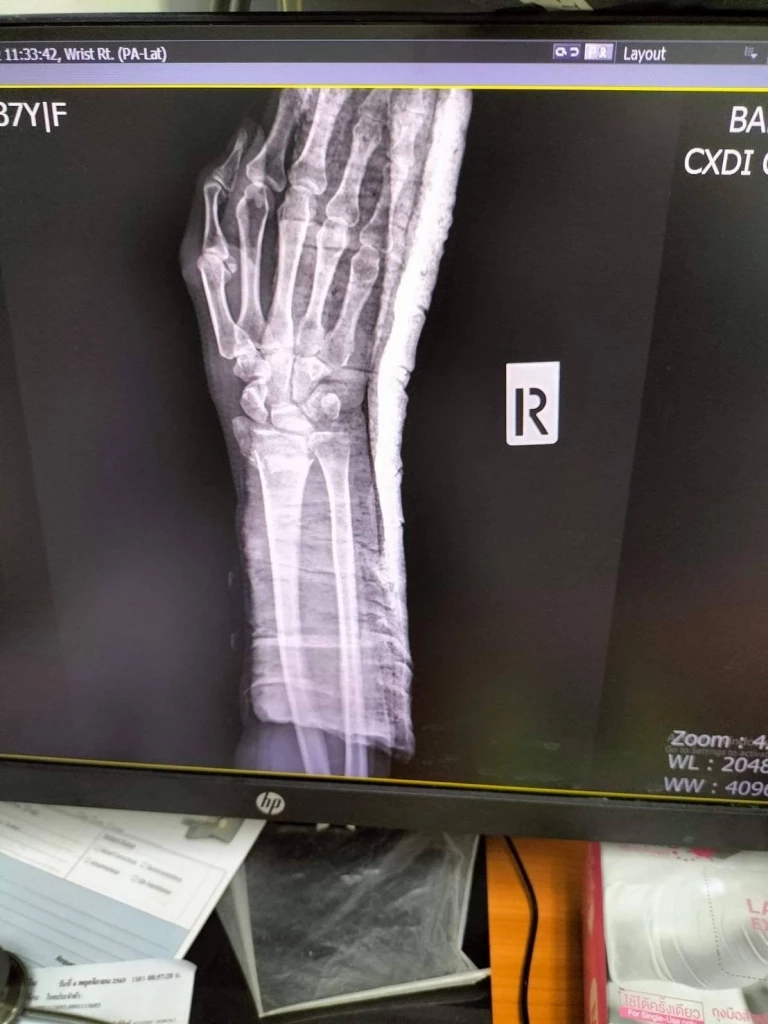

สจ.ได้ลงมาเรียกแฟนหนุ่มไป แล้วพูดว่า "กูขอตบหน้าทีนึงได้มั้ย หมั่นไส้ มึงแอ็คจัง" แฟนหนุ่มก็ยอมก้มหัวจะให้ตบ แต่ตนพูดขึ้นว่า "ตบไม่ได้ แฟนหนู ไม่ได้ทำอะไรผิด" จากนั้น สจ. ก็พูดว่า "งั้นเดี๋ยวกูจะตบทั้งคู่นี่แหละ” หลังจากนั้น สจ. ก็ได้เดินมาผลักตนอย่างเต็มแรงจนล้มและข้อมือหัก ต่อมาแฟนได้พาไปส่ง รพ. ซึ่งหมอแจ้งว่ากระดูกแตกและหัก ต้องผ่าตัดดามเหล็ก